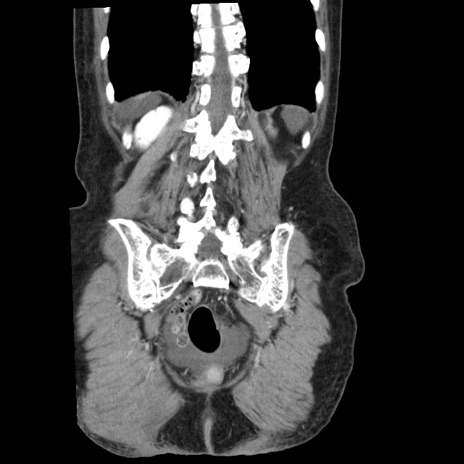

横断像